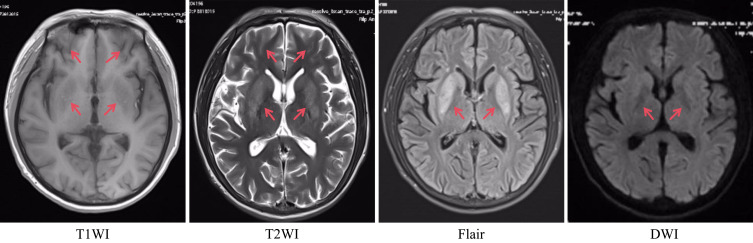

Case presentation: We report two patients undergoing regular hemodialysis for end-stage renal disease who presented with progressively intensified involuntary limb movements. Treatment with sedatives alone proved ineffective in both cases. Through differential diagnosis, one patient was diagnosed with diabetic striatopathy and managed with intensive glycemic control, while the other was found to have uremic metabolic encephalopathy and treated with a combination of hemodialysis and hemoperfusion. Subsequently the patients' symptoms improved significantly.